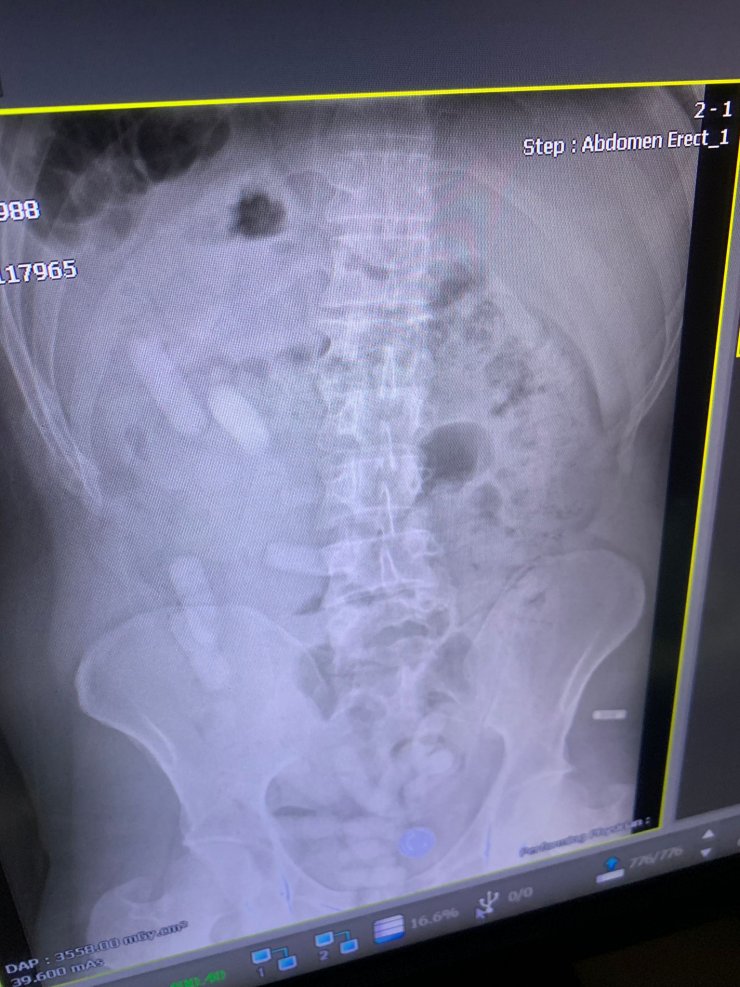

SİVAS'ta yolcu otobüsünde İranlı yolcunun üzerinde ve midesinde toplam 1 kilo 395 gram reçine esrar ile 6 uyuşturucu hap ele geçirildi. Midedeki esrarın 15 paket halinde olduğu belirtildi.